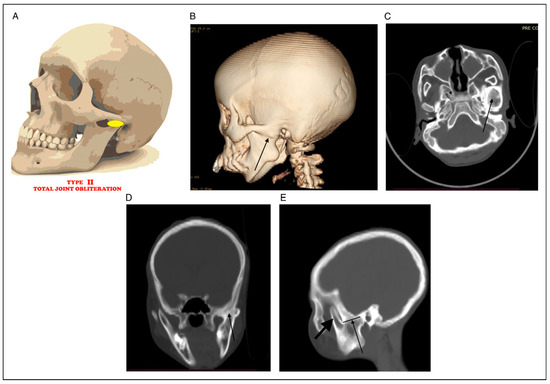

Braimah-Taiwo et al. New Classification System and Treatment Algorithm of Mandibulo-Maxillary Synostosis Related to Noma. Field Experience From Noma Children Hospital Sokoto, Nigeria

Study Design: This was a retrospective study at Noma Children Hospital, Sokoto, Nigeria, from January 2018 to December 2021. Objective: The main objective of this appraisal was to present Braimah-Taiwo et al.’s new classification system for mandibulo-maxillary synostosis secondary to noma and also [...] Read more.

Study Design: This was a retrospective study at Noma Children Hospital, Sokoto, Nigeria, from January 2018 to December 2021. Objective: The main objective of this appraisal was to present Braimah-Taiwo et al.’s new classification system for mandibulo-maxillary synostosis secondary to noma and also to provide a guide to their treatment. Methods: Noma with mandibulo-maxillary synostosis was the main inclusion criteria. Excluded were cases of acute noma and noma without mandibulo-maxillary synostosis. Data retrieved include demographics of patients and extent of bony ankylosis and mandibulo-maxillary synostosis. Results: A total of 64 patients (30 (46.9%) males and 34 (53.1%) females) were managed. Ages ranged from 6 to 40 years with mean ± SD (18.2 ± 7.6) years. Regarding the new classification system of mandibulo-maxillary synostosis, 6 (9.4%) patients presented with Type 1 (Mild joint obliteration) ± Soft tissue scarring, 24 (37.5%) presented with Type II (Total joint obliteration) ± Soft tissue scarring, 21 (32.8%) presented with Type III (Coronoid, zygoma and maxilla) ± Soft tissue scarring, 4 (6.3%) presented with Type IV (Condyle, glenoid fossa, coronoid, sigmoid notch and zygoma) ± Soft tissue scarring, 7 (10.9%) presented with Type V (Condyle, glenoid fossa, coronoid, sigmoid notch, zygoma and pterygo-maxilla) ± Soft tissue scarring, while 2 (3.1%) patients presented with Type VI (condyle, glenoid fossa, coronoid, sigmoid notch, zygoma, pterygo-maxilla and the orbit) ± Soft tissue scarring. Conclusions: Pattern of tissue destruction in noma patients is complex involving both soft and hard tissues. This new classification will guide surgeons in the effective management of these patients. Full article